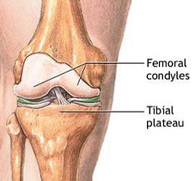

Fracturas del tercio inferior del fémur

Las fracturas en el tercio inferior del fémur son poco frecuentes. Pueden afectar al paciente joven tras un traumatismo de alta energía y al paciente anciano tras una simple caída casual debido al déficit de calcio a este nivel.

Al tratarse de fracturas articulares suponen un desafío terapéutico para el cirujano dado que la restitución de la anatomía debe ser exquisita para evitar complicaciones posteriores. Actualmente y gracias a los avances en traumatología mínimamente invasiva pueden restaurarse estas fracturas a través de pequeños abordajes percutáneos que minimizan la lesión musculocutánea favoreciendo una recuperación más rápida y confortable.